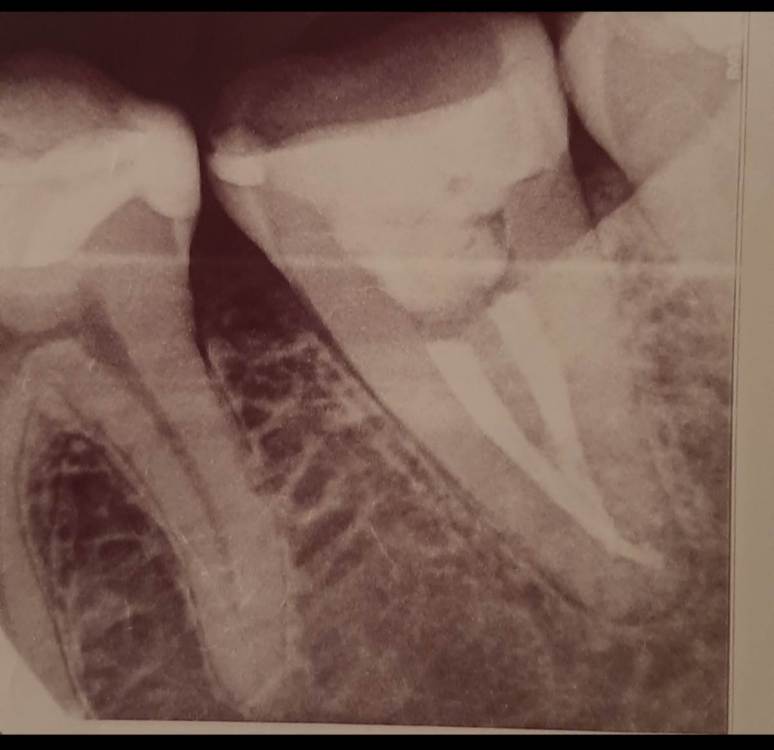

Лана-Лана Опубликовано 6 декабря, 2021 Поделиться Опубликовано 6 декабря, 2021 (изменено) Добрый день. Установили цирконевую коронку на нижнюю семёрку, при примерке я заметила что коронка низкая , но врач убедила что все впорядке типа мой зуб такой и был, самый последний бугор на контакте с восмым зубом с язычной стороны чуть ли не на уровне десны. Теперь когда жуешь и туда попадает что то твердое мясо, яблоко очень больно десну .. я сказала об этом ортопеду но она говорит что по другому не сделать, и предлагает вырвать восьмёрку и засчет этого опустится десна, но это же не выход , да и не хочу я ее удалять, раньше у меня с моим натуральным зубом таких проблем не было.... посмотрите пожалуйста снимки зуба до и фото после, действительно ли у меня был такой низкий зуб? Или это портак? На фото во рту видно что он ниже восьмёрки а край с язычной стороны ещё ниже...и если это плохо сделанно? Можно ли просить переделки ведь он ещё на гарантии? Или это проблемно снять? И что вообще в таких случаях делать если ортопед отказывает в переделке? Писать претензию? Изменено 6 декабря, 2021 пользователем Лана-Лана Ссылка на комментарий